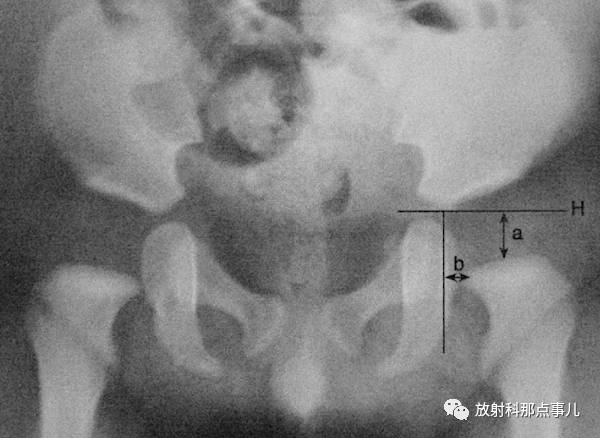

骨盆正位片上,两侧Y形软骨中心连线与髋臼上下缘连线所形成的夹角。正常值新生儿为30° ,1岁以后不应超过25° ,2岁时为20° ,成人为10° 。先天性髋关节脱位时髋臼变浅,髋臼角增大。(上图中角a)

髂骨角

髂前下棘和髋臼外上缘间连线与Y形软骨水平线的夹角。新生儿为55° ,正常值范围在43° ~67° ,角度减小提示异常,如骨质软化症。(上图中角b)

新生儿髋关节间隙

新生儿骨盆正位片,通过两侧髋臼Y形软骨作连线称为Hilgenreiner线,简称H线。股骨上端距H线之间距离称为上方间隙,股骨上端鸟嘴距坐骨支外缘之间的距离为内侧间隙,正常值上方间隙为9.5mm,内侧间隙为4.3mm,若上方间隙小于8mm,内侧间隙大于5.1mm,应怀疑髋关节脱位。若上方间隙小于7.5mm,内侧间隙大于6.1mm,可诊断为髋关节脱位。